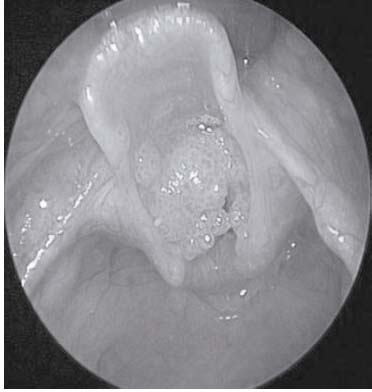

La niña fue clasificada como American Society of Anesthesiologists (ASA) III para la realización de fibrolaringoscopía flexible. El ayuno fue de seis horas previas al procedimiento. Se evitó sedación preoperatoria, anticipando dificultad en el manejo de las vías respiratorias se preparó tubo endotraqueal de pequeño tamaño (ET), tubos de traqueotomía y equipo de reanimación. La monitorización fue la de rutina (electrocardiografía, SpO 2, presión arterial no invasiva, capnografía). Se administró atropina intravenosa (IV) 10 ?g y hidrocortisona 25 mg antes de la inducción. La inducción se realizó con oxígeno al 100% midazolam 0,1 mg/kg, propofol 2 mg/kg y ketamina 0,1 mg/kg. Tras lograr un plano más profundo de anestesia (respiraciones más superficiales y frecuentes) se procedió con la administración lidocaína 1% rociada en la vía aérea especialmente las cuerdas vocales (cubiertas por el tumor) durante la inspiración, este procedimiento se realizó guiado por laringoscopia. La neumóloga introdujo el fibrolaringoscopio a través de la máscara de Patill y guiada por la apertura de las cuerdas vocales durante la respiración espontánea obtuvo muestra para biopsia del tumor. Se evidenció múltiples papilomas sobre ambas cuerdas vocales falsas, algunos pendulares que obstruían la apertura laríngea en un 80% ( Figuras 2).